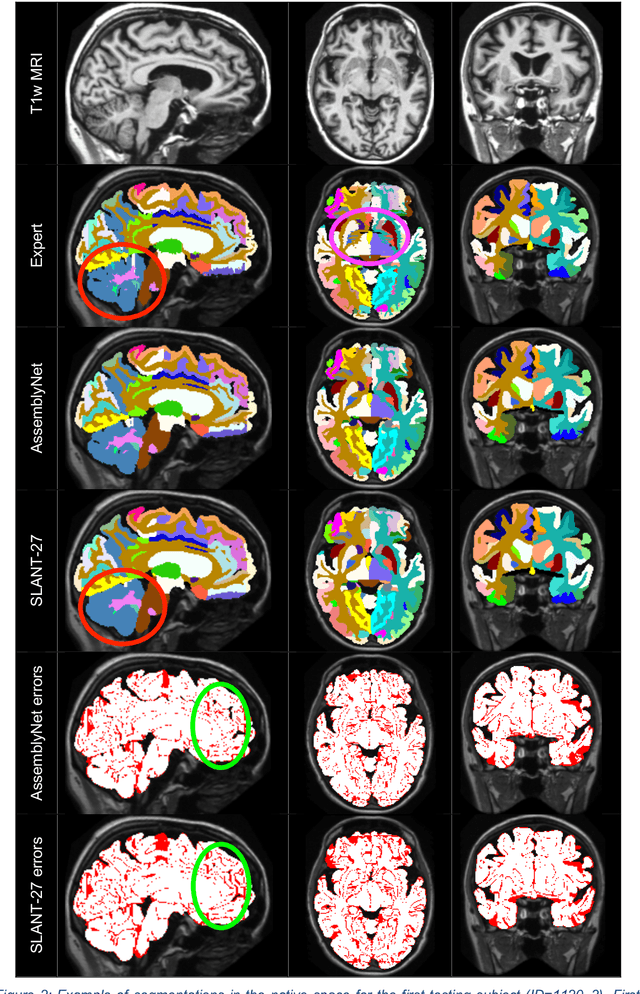

Abstract:Whole brain segmentation using deep learning (DL) is a very challenging task since the number of anatomical labels is very high compared to the number of available training images. To address this problem, previous DL methods proposed to use a single convolution neural network (CNN) or few independent CNNs. In this paper, we present a novel ensemble method based on a large number of CNNs processing different overlapping brain areas. Inspired by parliamentary decision-making systems, we propose a framework called AssemblyNet, made of two "assemblies" of U-Nets. Such a parliamentary system is capable of dealing with complex decisions, unseen problem and reaching a consensus quickly. AssemblyNet introduces sharing of knowledge among neighboring U-Nets, an "amendment" procedure made by the second assembly at higher-resolution to refine the decision taken by the first one, and a final decision obtained by majority voting. During our validation, AssemblyNet showed competitive performance compared to state-of-the-art methods such as U-Net, Joint label fusion and SLANT. Moreover, we investigated the scan-rescan consistency and the robustness to disease effects of our method. These experiences demonstrated the reliability of AssemblyNet. Finally, we showed the interest of using semi-supervised learning to improve the performance of our method.

Abstract:Whole brain segmentation using deep learning (DL) is a very challenging task since the number of anatomical labels is very high compared to the number of available training images. To address this problem, previous DL methods proposed to use a global convolution neural network (CNN) or few independent CNNs. In this paper, we present a novel ensemble method based on a large number of CNNs processing different overlapping brain areas. Inspired by parliamentary decision-making systems, we propose a framework called AssemblyNet, made of two "assemblies" of U-Nets. Such a parliamentary system is capable of dealing with complex decisions and reaching a consensus quickly. AssemblyNet introduces sharing of knowledge among neighboring U-Nets, an "amendment" procedure made by the second assembly at higher-resolution to refine the decision taken by the first one, and a final decision obtained by majority voting. When using the same 45 training images, AssemblyNet outperforms global U-Net by 28% in terms of the Dice metric, patch-based joint label fusion by 15% and SLANT-27 by 10%. Finally, AssemblyNet demonstrates high capacity to deal with limited training data to achieve whole brain segmentation in practical training and testing times.